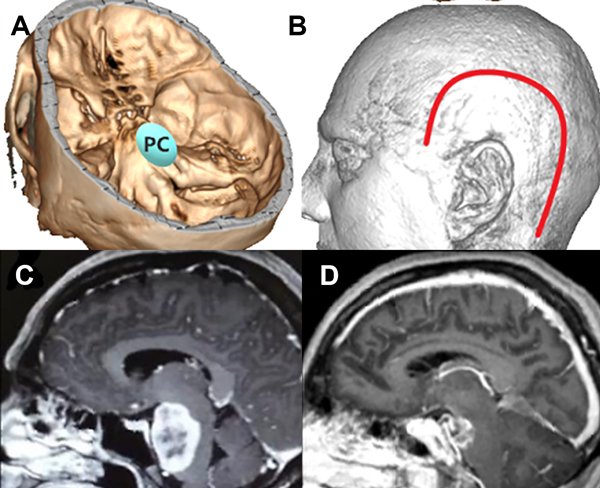

Luego del análisis estadístico propusimos una escala de graduación preoperatoria, con la cual según el puntaje total obtenido podemos inferir la probabilidad de exéresis total. Para la escala utilizamos la localización, el tamaño y la invasión ósea como parámetros (Figura 3, 4 Y 5).

Figura 5: Paciente con meningioma de base de cráneo petroclival (PC) (2 puntos), en su diámetro máximo midió 5 cm (2 puntos) sin invasión ósea, total: 5 puntos, baja probabilidad de resección total. A: localización de lesión en base de cráneo. B: abordaje realizado combinado. C: resonancia con contraste corte sagital prequirúrgica. D: resonancia con contraste corte sagital posquirúrgica con resección subtotal de lesión.